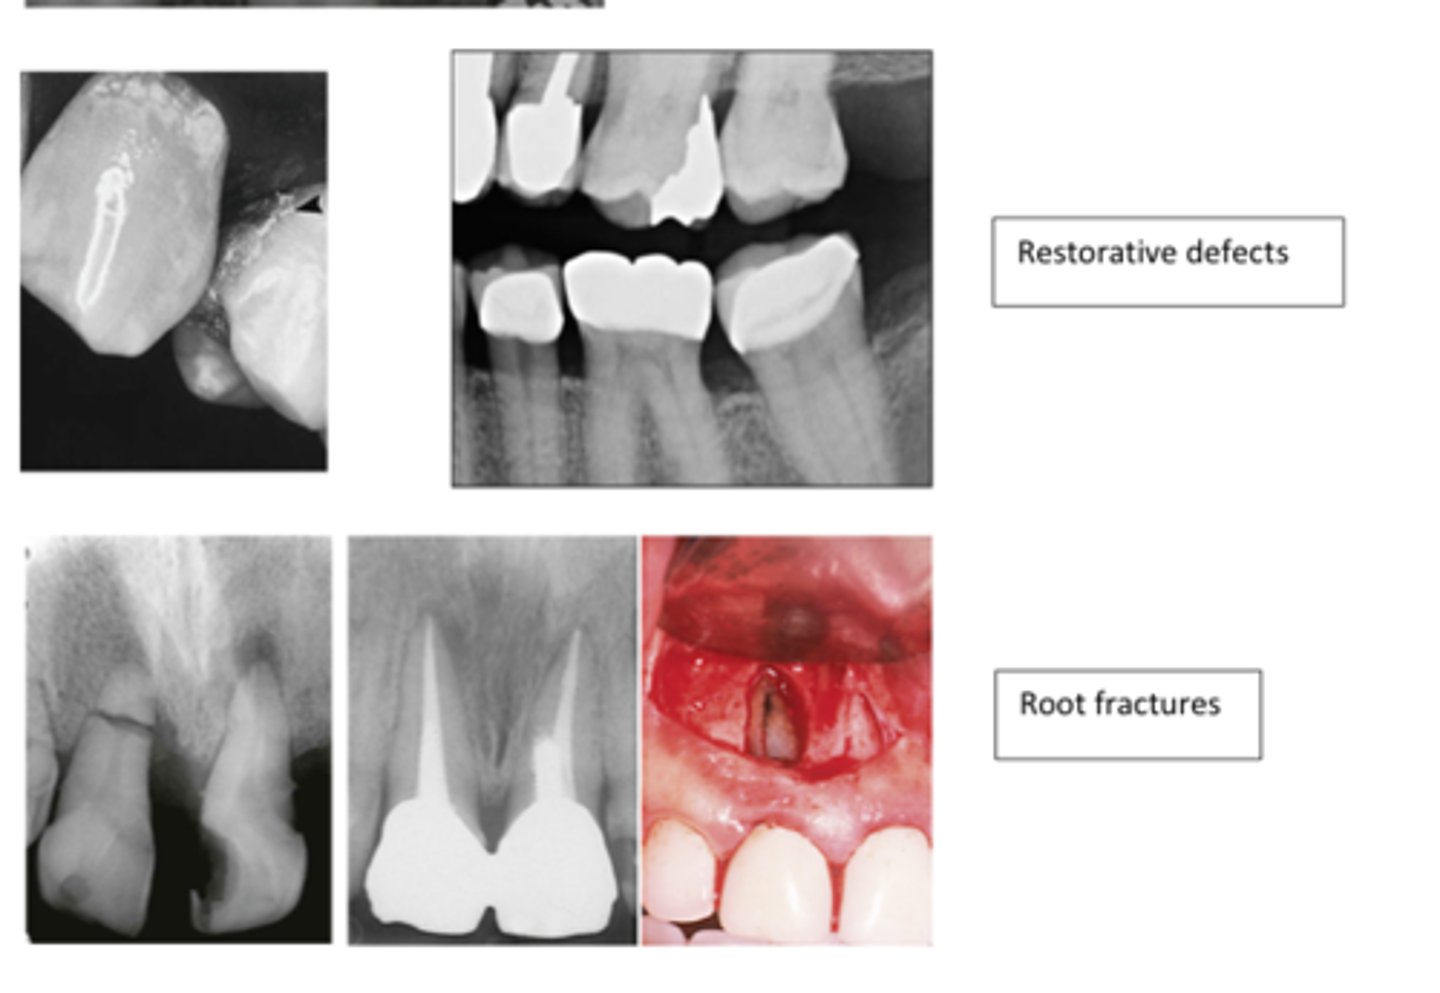

Permits the transmission of X-rays

Appears black:

- composite resin

- procelain

Any substance that blocks the transmission of x-rays

Appears white:

- silver amalgam

- gold

- CaOH

- pins & posts

- Gutta percha

- SSC

- implants

Radiolucent=

Radiopaque=

Radiolucent

Porcelain shows up (radiolucent/radiopaque) on a radiograph